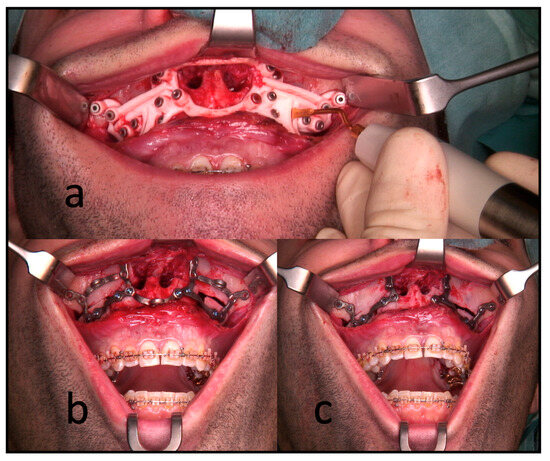

2.4. Operation and Techniques

All the surgeries were performed by the authors, CF or RK, under general anesthesia. In the segmental maxillary osteotomies with PSI, the intraoral incision was extended from the first molar’s vestibulum to the other quadrant’s first molar. This was followed by subperiosteal preparation and denudation of the maxilla. Subsequently, the drilling and cutting guide was placed. After fixing this guide with 1.5 mm screws, the guided drilling was conducted by drilling along the metal tubes with a 1.1 mm drill for a 1.5 mm screw osteosynthesis. The horizontal osteotomy of the Le Fort I osteotomy and the inter-radicular osteotomies were conducted by piezo-osteotomy (Figure 3). Patient-specific implants fabricated by KLS Martin (KLS Martin, Tuttlingen, Germany) were used to position both the maxilla and the segments to each other with 1.5 mm screws without using a surgical splint.

Figure 3. Intraoperative use of PSI for a three-piece maxilla. (a) Drilling and cutting guide: the piezo osteotome is used to conduct interradicular osteotomies. (b) The full arch patient-specific implant is used to position and osteosynthesize the maxillary segments without a surgical splint. Note the infraorbital and medial connection bars. (c) The connection bars are removed, leaving the patient with interconnected individual L-plates.